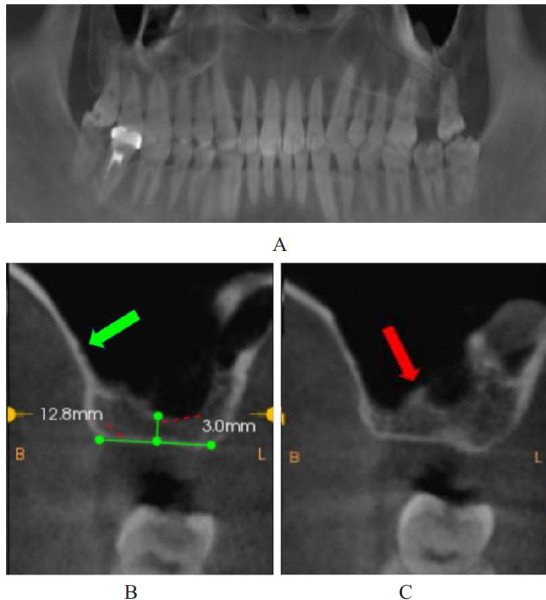

ABSTRACT Transalveolar technique for sinus floor elevation(TSFE) offers the advantages of minimal invasiveness,reduced postoperative reaction,and shorter operative time for vertical bone augmentation in the maxillary posterior region.The clinical data of one patient with severe deficiency of residual bone height (RBH)in the maxillary posterior region,a blood vessel visible in the lateral wallof the maxillary sinus anda visible septum at the floor of the maxillary sinus were reported,and two-stage flexible TSFE was used to improve the vertical bone height of the operated area while reducing trauma,the risk of Schneiderian membrane rupture and maxilary sinus infection,etc.,and the relevant literatures were reviewed.The patient,male,26 years old,complained of missing left maxillary posterior teeth for more than 1 year and requested restoration. The patient had 27 missing teeth,normal keratinized gingiva,full alveolar ridge,no elongation of the opposing teeth,fair width of the proximal and normal occlusal distance.The results of cone beam CT(CBCT) showed that the distance between the sinus crests at the site of the 27 teeth was about 3mm ,thewidth of the alveolar bone was about 12.8mm ,the bone density was normal,and there were no residual roots or other abnormalities;no cyst-like lesions were seen in the wals of the maxillary sinuses bilaterally,and separation was seen at the floor of the maxillary sinus on the left sideand a blood vessel was seen in the lateral wall of the maxillary sinus.A diagnosis of Kennedy class II maxillary tooth defects was made.After two stages of TSFE,the Schneiderian membrane was intact and the bone height of the implant area was elevated to 9.6mm from 3mm preoperatively after the completion of the restoration,with stable bone augmentation,good osseointegration,and restoration of normal occlusal function.For the patients with severe bone height deficiency in the maxilary posterior region,flexible two-stage TSFE should be considered,whichcan help to reduce the risk of maxillary sinus infection and Schneiderian membrane rupture while minimizing the damage and obtaining the ideal bone augmentation results.